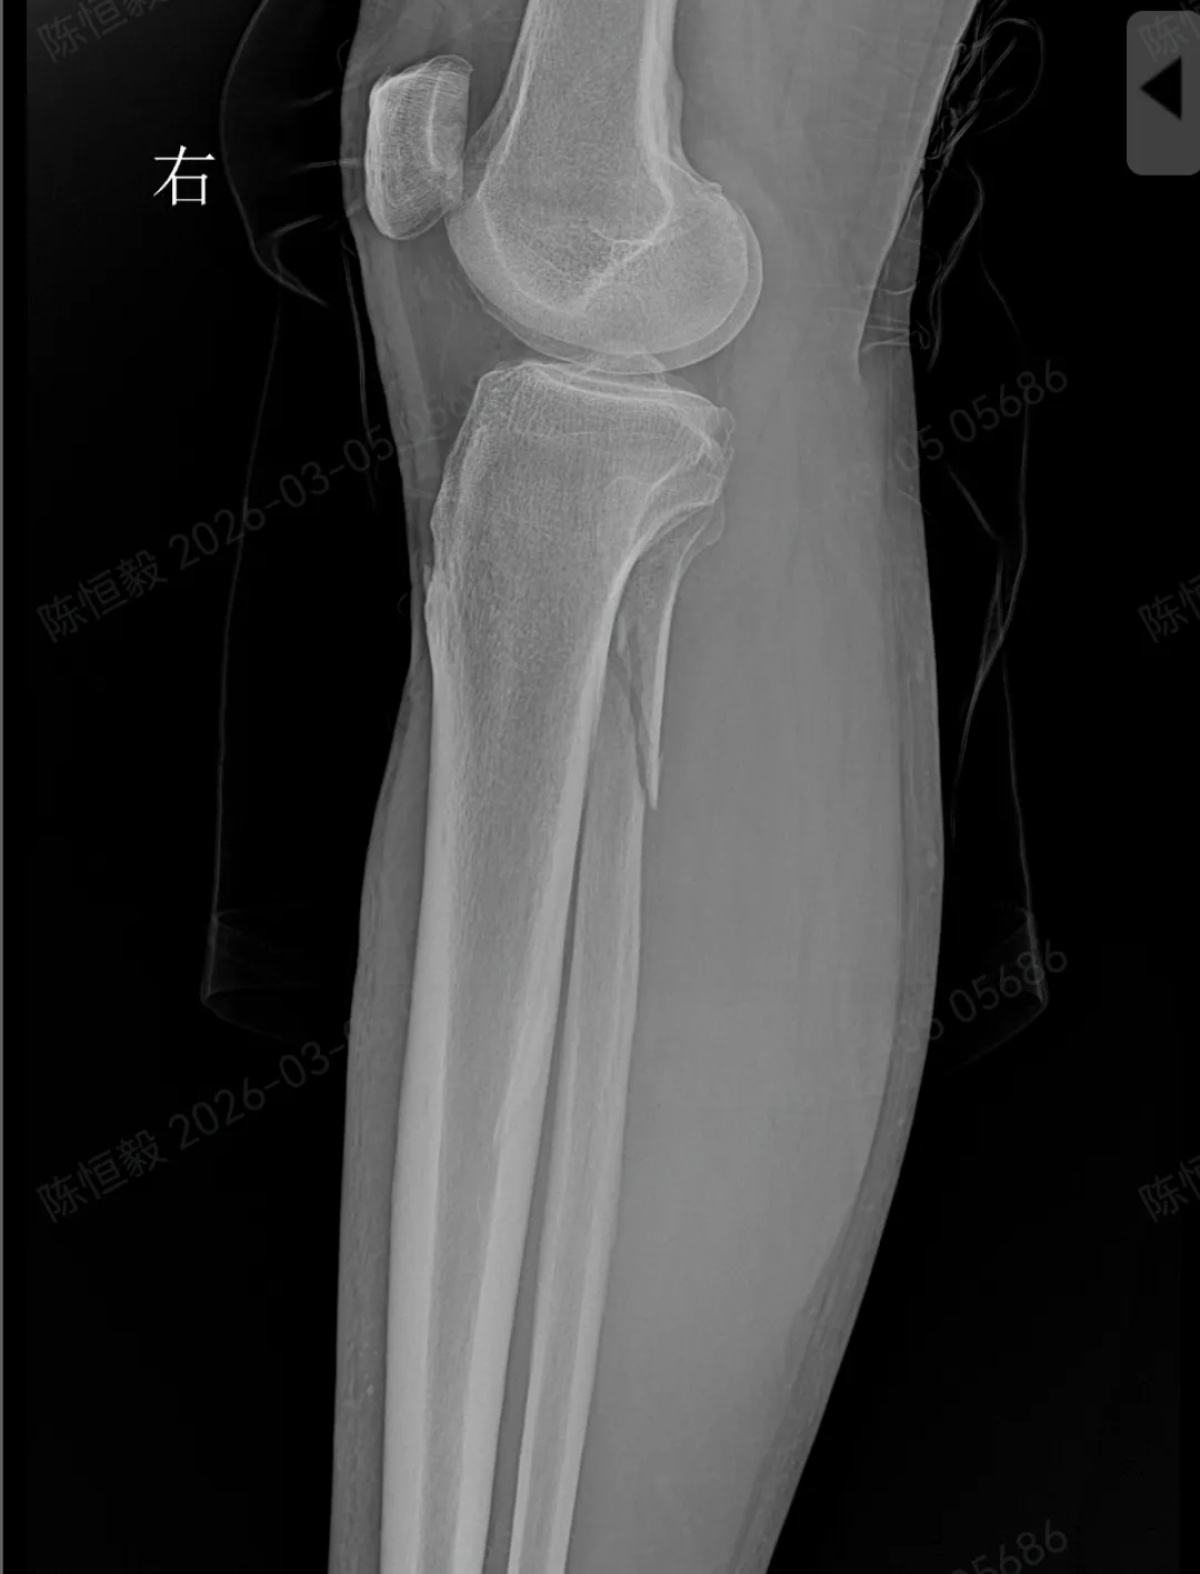

王大爷听从建议住院后,经完善体格检查及 CT 检查,最终确诊为复杂的 Maisonneuve 骨折:不仅存在下胫腓分离,还合并前踝 Chapute 结节撕脱骨折、后踝骨折、内踝骨折,同时伴有腓骨高位骨折。

受访者供图

这类联合损伤必须通过手术治疗,若延误干预,后续极易引发创伤性关节炎、踝关节不稳定,严重影响正常行走功能。随后,医疗团队为王大爷开展手术治疗。

术中进行下胫腓拉力试验结果呈明显阳性,且复位效果未达预期,团队当机立断决定切开探查,发现前结节骨折块嵌顿于下胫腓间隙,正是阻碍复位的关键,取出骨折块后顺利完成复位,手术按规范流程顺利结束。